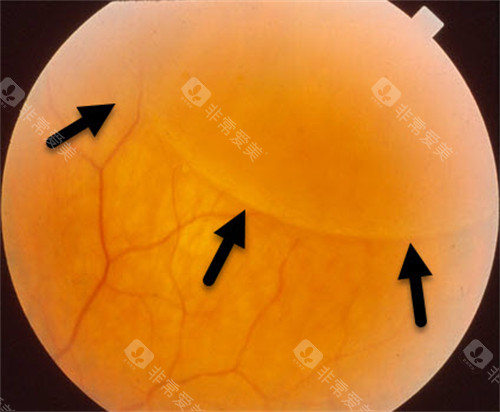

作为首都医学大学附属北京同仁医院眼底病科的“定海神针”,他擅长复杂眼底病诊疗,尤其对视网膜脱离、糖尿病视网膜病变等疾病的手术处理堪称业内标杆。